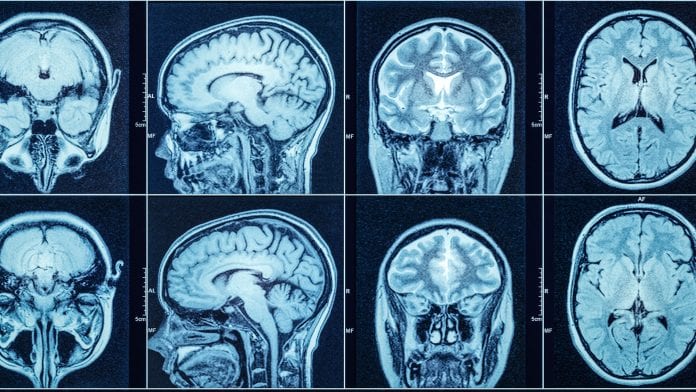

The new method uses magnetic resonance imaging (MRI) to provide accurate information about each individual and acts as an effective diagnostic aid tool.

The images are evaluated to determine the type of disease and the damaged area in the brain, following which an appropriate treatment protocol is recommended.

“A collection of data from different patients with disorders in this field has been collected, which includes structural, functional and structural-functional images,” said Mohammad Reza Nazemzadeh, a faculty member of Tehran University of Medical Sciences.